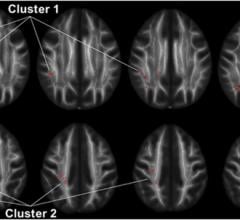

In a new study published in the journal Neuropsychopharmacology, neuroscientists from the University of Chicago show that white matter in a region of the brain called the superior longitudinal fasciculus (SLF) has less integrity and density in people with intermittent explosive disorder (IED) than in healthy individuals and those with other psychiatric disorders.